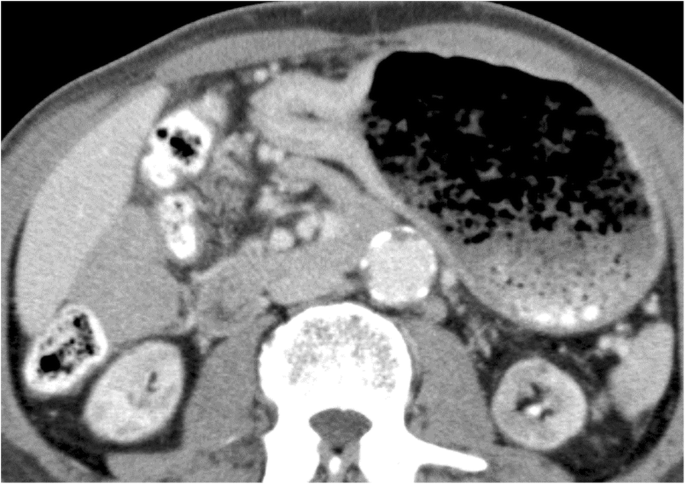

A 70-year-old man presented with anorexia and dysphagia. His past medical history was notable for type 2 diabetes, hypertension, chronic kidney disease requiring hemodialysis, and CCE. The CCE was triggered by a percutaneous coronary intervention in the context of myocardial infarction 7 years earlier. He had no history of smoking or alcohol abuse. Physical examination revealed cyanosis of both feet with dry gangrene of the distal toes but no livedo reticularis. The initial laboratory test results revealed a serum hemoglobin level of 8.0 g/dL, total white cell count of 9850/μL with 5.9% eosinophils (absolute eosinophil count, 581/μL; normal value < 500), serum carcinoembryonic antigen level of 3.2 ng/dL, and carbohydrate antigen 19–9 level of 15.3 ng/dL. Endoscopic examination revealed a type 4 tumor (Borrmann classification) circumferentially located, with invasion of the pyloric ring (Fig. 1). Biopsy revealed a poorly differentiated adenocarcinoma. Non-contrast computed tomography (CT) of the abdomen revealed focal circumferential wall thickening of the prepyloric antrum (T3) with several enlarged perigastric lymph nodes (N1) (Fig. 2) without any evidence of metastasis (M0). He underwent distal gastrectomy with Billroth 2 reconstruction. The right and left gastroepiploic arteries and right and left gastric arteries were resected, but the splenic and short gastric arteries were preserved. Lymph node dissection D2 was also performed. Postoperative histopathological findings revealed a poorly differentiated adenocarcinoma with a TNM score of pT4aN0M0. Several cholesterol emboli were found within the gastric arterial walls (Fig. 3).

On postoperative day 11, the patient developed abdominal pain without fever. Laboratory data revealed leukocytosis (white blood cell count: 17,190/μL) and an increased C-reactive protein level (21.13 mg/dL). Abdominal CT demonstrated a gastric wall discontinuity of the remnant stomach with fluid collection in the left subphrenic space. Gastric remnant necrosis was suspected, and an emergency laparotomy was performed.